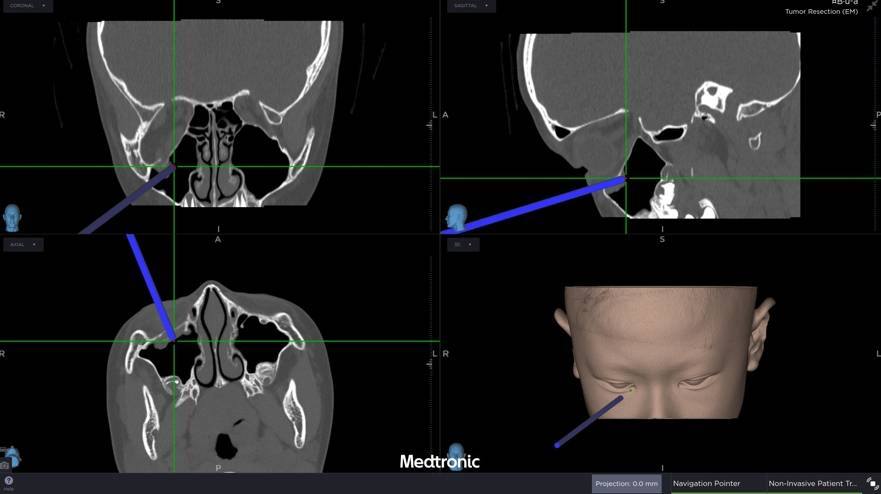

中山醫學大學附設醫院口腔顎面外科醫療團隊邱昱瑋主治醫師、張芳語主治醫師及洪珮瑄主治醫師,評估後,立即制定手術方案,運用創新電腦數位模擬技術,術中搭配內視鏡與精密導航系統,精準定位眼底嵌頓肌肉的位置,成功將被夾住的眼底肌肉復位。術後,患者複視症狀消失,眼球活動恢復正常。

張芳語醫師補充,重建受損眼眶骨在臨床上挑戰重重,包括手術視野狹小、骨頭型態複雜、手術精準度要求高,以及術後疤痕與外觀重建的考量,透過精準的數位導航技術,醫師團隊能克服這些困難,幫助患者安全恢復功能與外觀,重拾自信與生活品質。